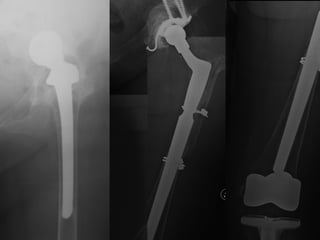

Paprosky

3-B (4)

Vanc. B - 3

21 mm

Subsidence

=

NO

LOOSENING

1999

1988

T 3 STEM